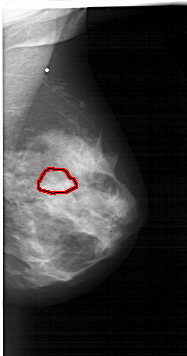

FILE: A_1566_1.RIGHT_MLO.OVERLAY

TOTAL_ABNORMALITIES 1

ABNORMALITY 1

LESION_TYPE MASS SHAPE LOBULATED MARGINS OBSCURED

ASSESSMENT 4

SUBTLETY 3

PATHOLOGY BENIGN

TOTAL_OUTLINES 1

BOUNDARY